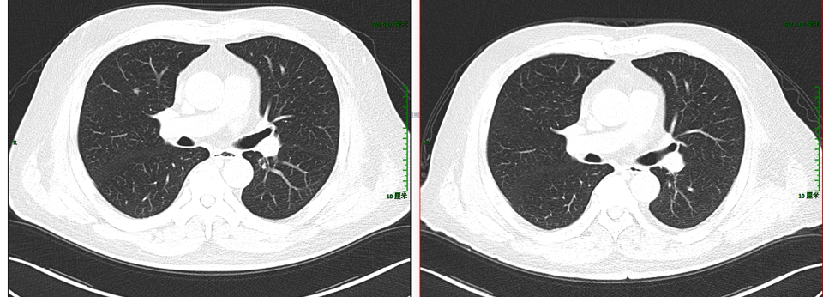

图示:2017-4 “直肠CA根治术+肝转移瘤切除术+胆囊切除术”后改变,直肠吻合口旁肠壁稍增厚;肝右后切缘旁低密度灶,较前片(2016-12-13)有所缩小,请结合临床并随访。

2017-4 我院PET-CT未见明确复发转移病灶:吻合口未见FDG代谢异常,肝右叶转移瘤术后,残余肝实质内FDG代谢未见异常,两肺野多发微小结节影,FDG代谢未见明显增高,考虑良性。